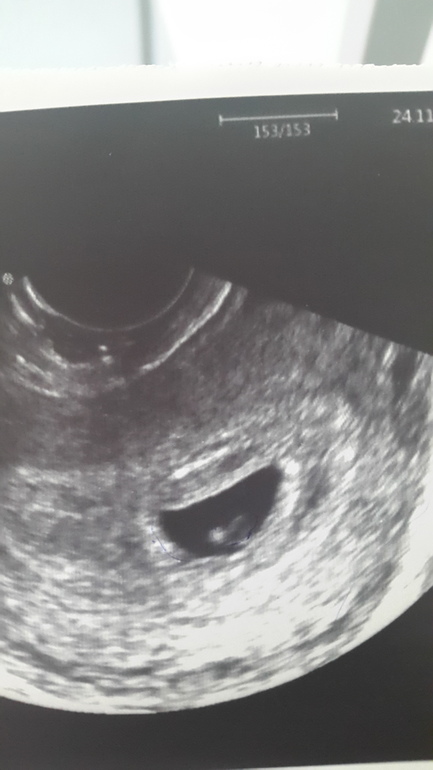

На этом узи крохе 5 недель.

Какое четкое фото... оболдеть... так хорошо видно... Ттт на вас и поздравляю :)